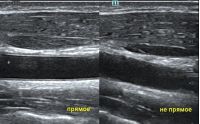

Ультразвуковая волна распространяется от пьезокристалла в направлении плоскости сканирования. Если волна отражается от поверхности исследуемой структуры под прямым углом и возвращается к пьезокристаллу напрямую, на сонограмме появляется четкая дифференцировка структуры и подчеркнутые контуры. Прямое отражение - самый важный критерий техники сканирования для измерения точных размеров органа. В случае отражения волны не под прямым углом эхогенность структуры меняется, дифференцировка на слои падает, контуры становятся нечеткими. Таким образом косой срез дает огромную погрешность измерения и затрудняет описание эхоструктуры объекта.

Как достичь прямого отражения Достаточно расположить объект на экране горизонтально, с помощью наклона датчика, чтобы волна отражалась от поверхности под прямым углом. При любом типе исследования любого органа или системы прямое отражение – залог достоверных результатов.